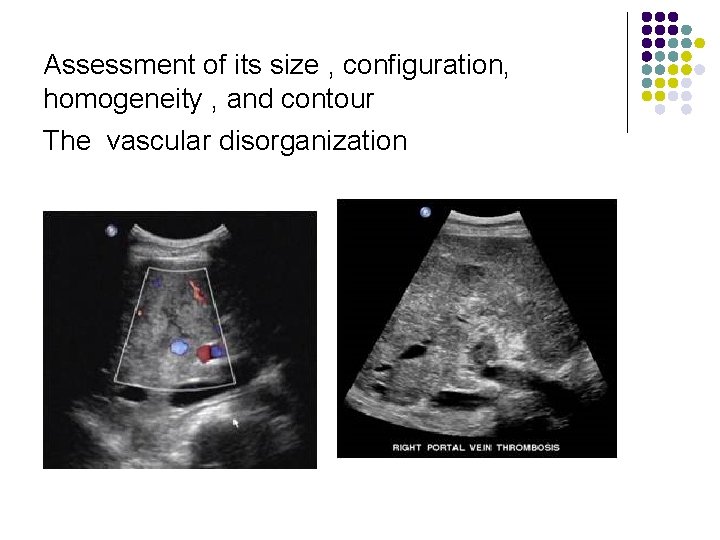

Assessment of its size , configuration, homogeneity , and contour The vascular disorganization